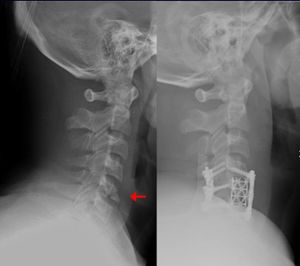

- جراحة العمود الفقري

- استئصال الصفيحة الفقرية Laminectomy

- سمكرة الفقرت القطنية.

- عمليات القرص بين الفقري في المنطقة القطنية.